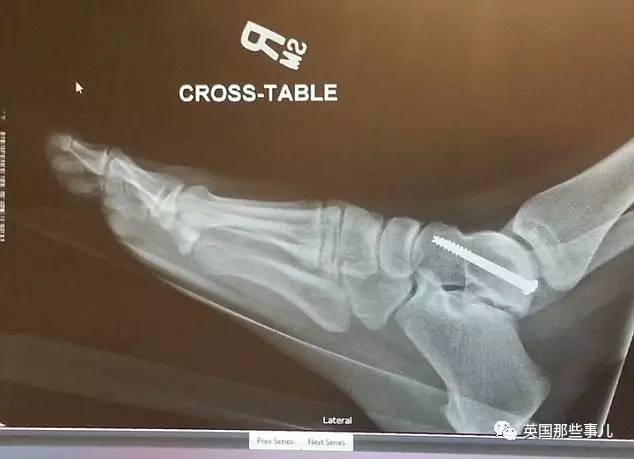

在那场车祸中,

Audra的鼻子被迎面甩过来的脚弄伤,

她的脚踝,

股骨的四个部分也被弹出的气囊硬崴至骨折...…

她的脚踝、臀部、膝盖上分别被打上了2个钢钉…